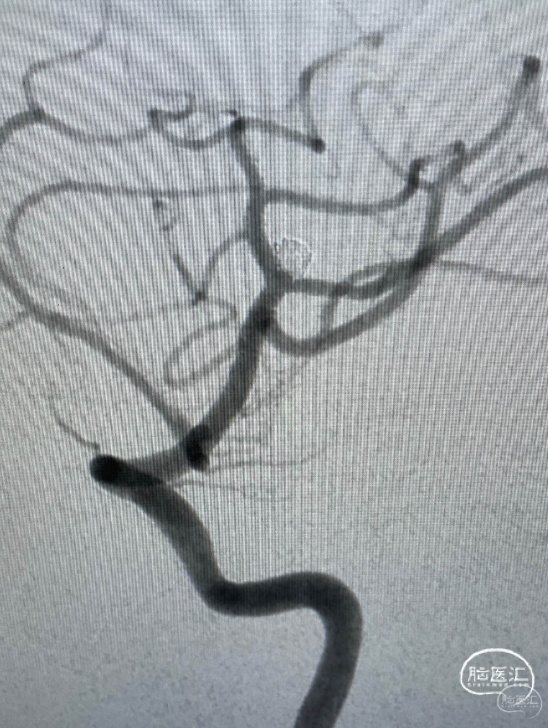

第一台手术结束。开始第二台,一个复发大脑中动脉瘤,复发部位虽然不大,但毕竟是出血动脉瘤,还是远期继续增大再出血的风险。

Lvis jr小支架辅助小弹簧圈栓塞,很好的解决的复发部分。

再次造影,没有动脉瘤的显影了,远期再复发的几率就很小了。